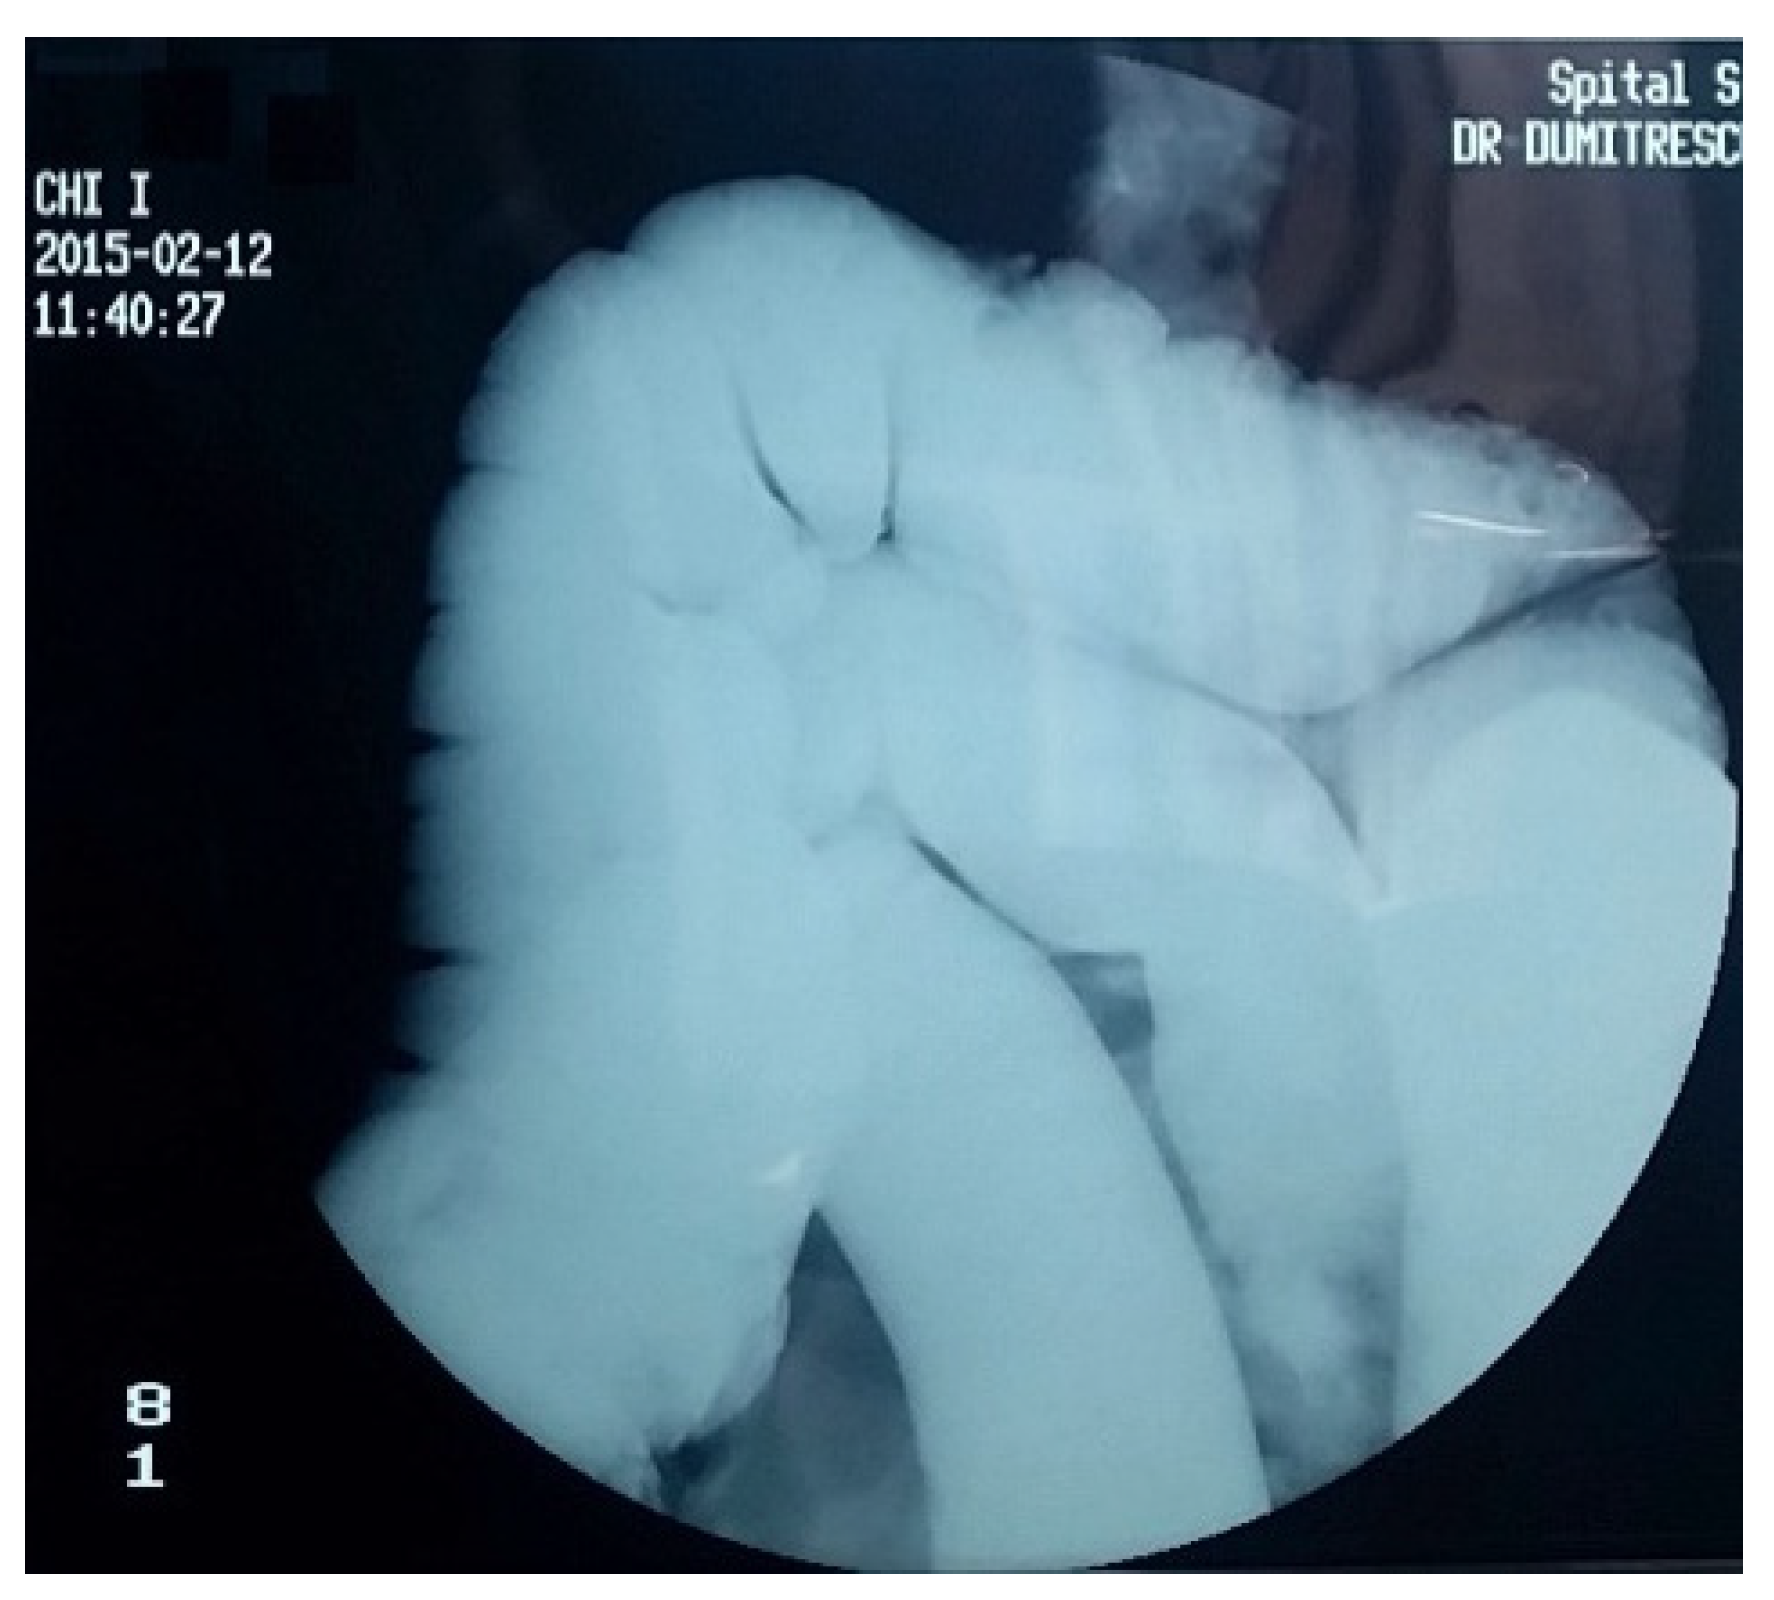

4. Diagnostic Criteria for the Acquired Megacolon